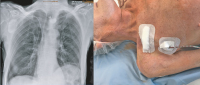

Herzchirurgie - Post-OP

Abbildung 3: Thorax-Röntgen und postoperatives Ergebnis. In Lokalanästhesie wird ein VVIR-Schrittmacher implantiert. Die Implantation verläuft komplikationslos. Postoperativ zeigt der Schrittmacher eine regelrechte Funktion.

Keywords: FotoHerzchirurgieKardiologiePost-OPThoraxröntgen